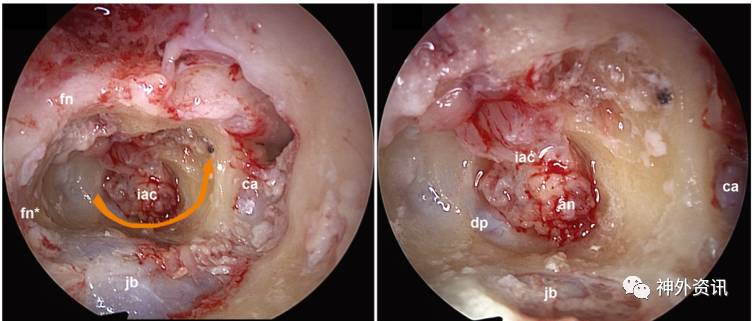

图2. EETTA手术图解。A.经外耳道入路,无皮肤切口;B.术前解剖标志;C.磨除耳蜗和听小骨后;D.磨除内听道,可见肿瘤;E.切除肿瘤;F.术毕,内耳道脂肪垫填塞。缩略词:an=听神经瘤(VS);ca=颈内动脉;et=咽鼓管;fn=面神经(鼓室段);fn*=面神经(乳突段);fn**=面神经(内听道段);fp=脂肪垫;gg=膝状神经节;in=砧骨;jb=颈静脉球;isc=外半规管;ma=锤骨;pr=鼓岬;s=镫骨;ve=耳前庭。以上图片版权归Daniele Marchioni所有。

图4. 右侧EETTA入路手术照片。左图:从外侧向内侧,在耳前庭下方沿内听道环磨除骨质,成马蹄形(橙色箭头),探查并打开内听道的前、下和后壁;右图:解剖内听道,直至打开内听道孔至颞骨内侧面的硬脑膜,到达小脑桥脑角区。缩略词:dp=内听道孔处的硬脑膜;其余见图2。